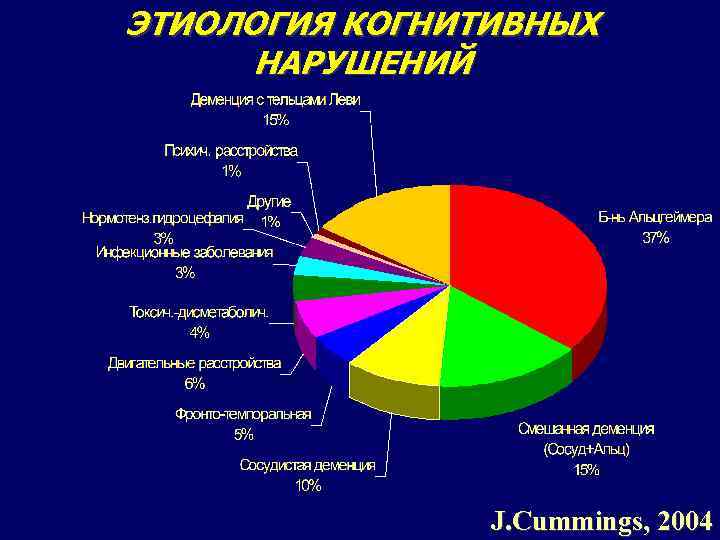

ЭТИОЛОГИЯ КОГНИТИВНЫХ НАРУШЕНИЙ 5 J. Cummings, 2004